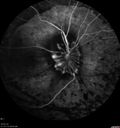

INDOCYANINE GREEN ANGIOGRAPHY: The indocyanine green angiogram similarly shows the leopard spots in the left eye and leakage from the lesion in the right eye.